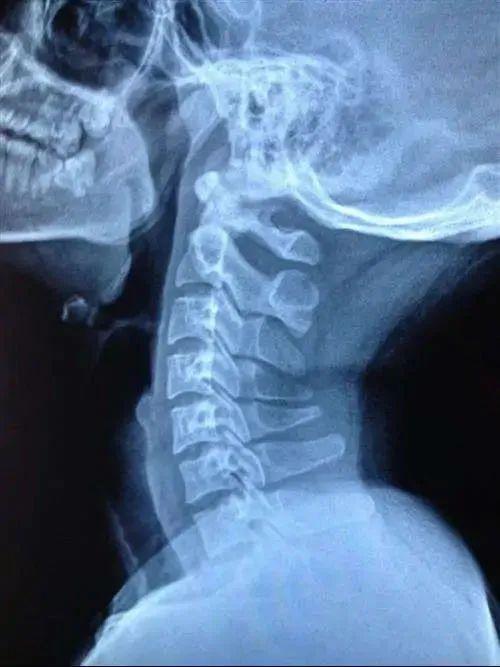

颈部生理曲度变直

低头时孩子头颈需保持前屈位置 , 使颈前屈肌持续收缩 , 颈后伸肌长时间被动牵伸得不到休息 。 长此以往颈部肌肉收缩功能逐渐减弱 , 肌力降低 , 韧带松弛退化 , 导致颈椎反拱形生理弯曲消失 , 颈椎变直 , 压迫神经 , 大脑供血不足引起眩晕等症状 。 虽然小儿颈椎病并不会导致椎间盘受损 , 但是如果不及时治疗 , 会影响孩子的生长发育 。